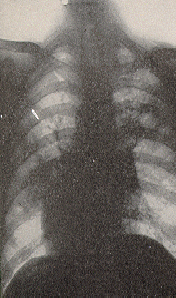

Xrays show almost humanoid skeletal structure. The bones of a leg are broken in several places.

Lungs are congested but that might be normal for the species. Notice the vertical elongation

of the rib cage. Chest skeletal structure appears intact.